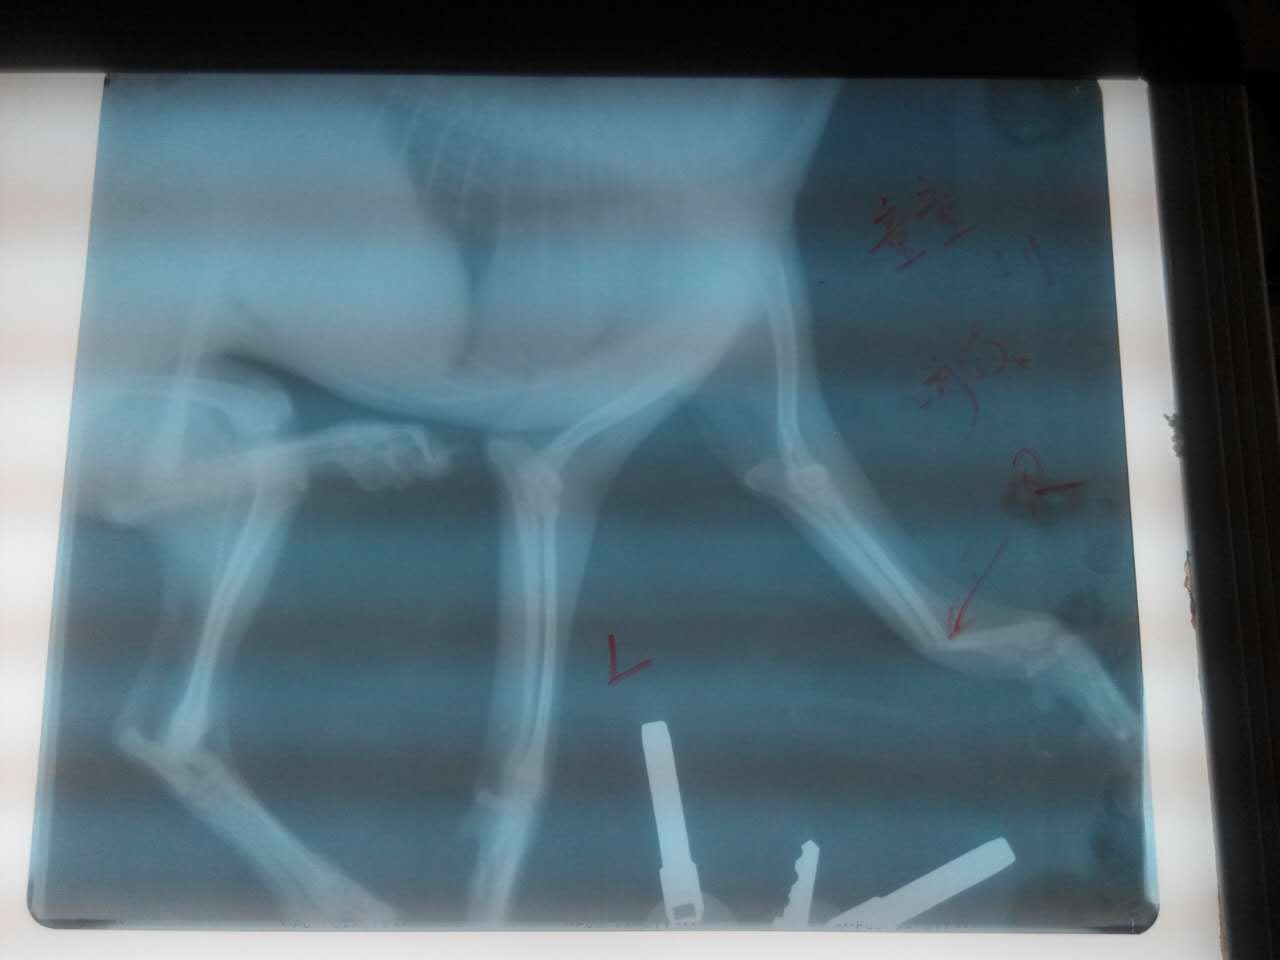

洛龍區(qū)元華國(guó)際,母泰迪犬童童從高處墜落己四天,X光片顯示右前肢前臂骨遠(yuǎn)端完全骨折,且呈100度背角移位。

精心治療中

經(jīng)整變固定,35天后痊愈。